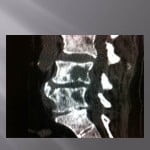

Biopsie sous guidage scanner